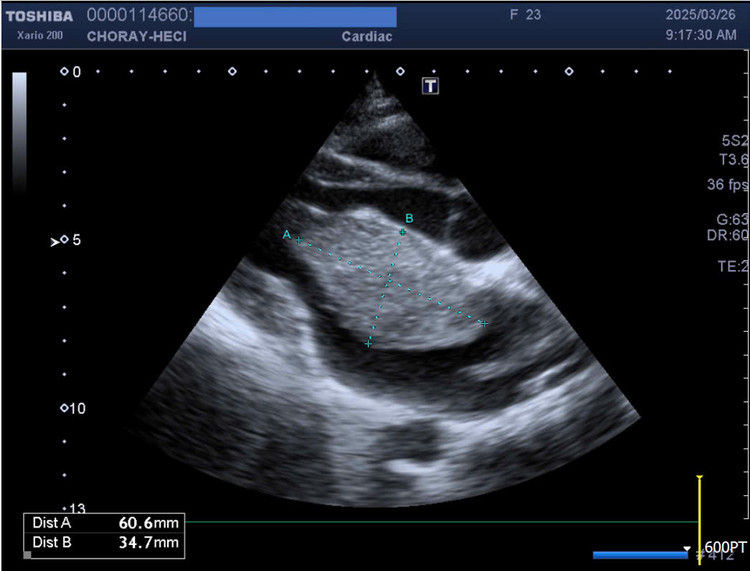

Bệnh nhân được đề nghị kiểm tra thêm siêu âm tim với kết quả ghi nhận có khối u đặc đồng nhất trong nhĩ trái nghĩ nhiều là u nhầy, kích thước khoảng 33*57mm, có cuống bám vào vách liên nhĩ, di động nhiều lan đến van 2 lá gây tắc nghẽn cơ học tại van và gây hở van mức độ nặng.

| Hình siêu âm tim ghi nhận khối u to, kích thước 33x57mm gây tắc nghẽn cơ học tại van 2 lá - Ảnh BVCC |